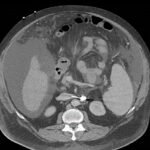

Endovascular coil embolization continues to become a more frequent modality of addressing hemorrhage and bleeding in patients. Migration refers to the coil unraveling or moving from the original embolization site. Migration of a coil is a known complication which can lead to serious consequences based on where the coil migrates. Despite increasing efforts to improve safety and technique, the risk of migration remains. We present a case of an embolization coil that migrated to the right ventricle, which was incidentally found roughly 2 months after undergoing an interventional radiology procedure for gastric variceal bleeding. The patient presented to the emergency department with dyspnea and abdominal pain. Unique images were obtained during his visit and in subsequent follow-up. As use of vascular embolization coils continues to become more commonplace, understanding the risks and complications of these procedures remains an important aspect of providing care for patients once they have left the interventional radiology suite. Coil migration should be a differential to consider in patients who present to the emergency department with signs or symptoms of arrhythmia or pulmonary embolism who have undergone a coil embolization procedure.